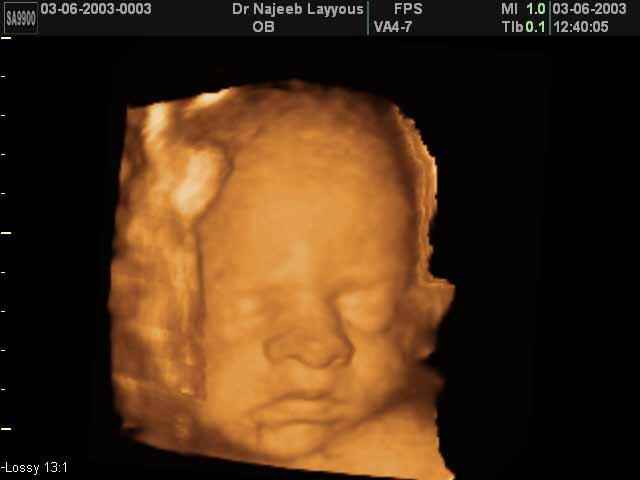

3D Fetal Face Ultrasound Scan Photos